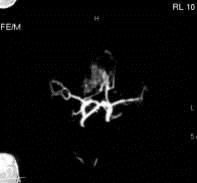

病历摘要:??患者男性,56岁,因右侧视力下降伴视野缺损2个月来院就诊,诉头痛,无明显头晕,无视物重影,无恶心呕吐,无肢体抽搐,无肢体乏力,胃纳佳,大小便...

问题 病历摘要:??患者男性,56岁,因右侧视力下降伴视野缺损2个月来院就诊,诉头痛,无明显头晕,无视物重影,无恶心呕吐,无肢体抽搐,无肢体乏力,胃纳佳,大小便正常,既往史无特殊,入院检查:神志清楚,言语清楚,体毛分布正常,左侧视力4.6,右侧视力4.0,粗侧右颞侧视野缺损,左侧正常,颈软,四肢肌张力正常,肌力正常,病理征(-)。 对于动脉瘤,下列那些是翼点入路的适应症?提示:该患者采用左侧翼点开颅夹闭动脉瘤

选项 A.颈内动脉-眼动脉动脉瘤 B.大脑前动脉动脉瘤 C.前交通动脉动脉瘤 D.颈内动脉末端动脉瘤 E.大脑中动脉动脉瘤 F.后交通动脉-颈内动脉动脉瘤 G.基底动脉末端动脉瘤

答案 ABCDEFG

解析 ABCDEFG